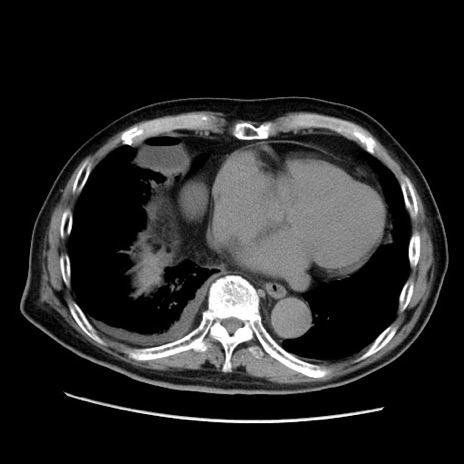

冠状断像

症例21(横断像)

【症例】70歳代男性

【現病歴】肝硬変・肝細胞癌にてかかりつけの方。約9時間前に食後より腹痛出現。症状が徐々に増悪し、嘔吐出現したため来院。

【既往歴】肝硬変、肝細胞癌(RFA、TACE後)